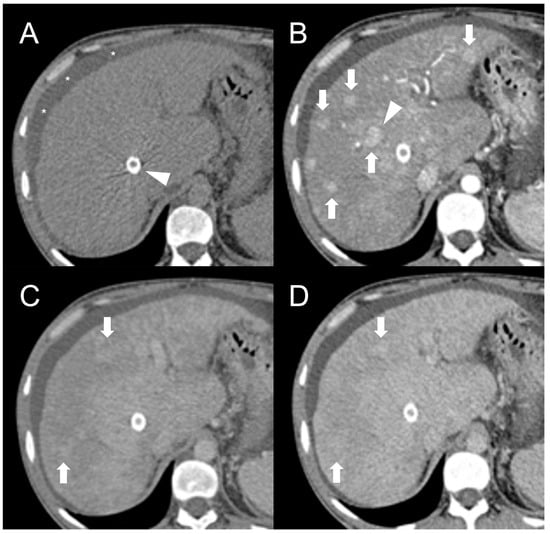

Finally, in BCS is possible to encounter pseudo-lesions. A typical example is the selective hypertrophy of the caudate segment (or any other segments with preserved venous drainage) in chronic BCS, which may take a tumor-like appearance (Figure 8) [50]. The hypertrophied segments may be hyperdense on unenhanced CT scan or exhibit T1-hyperintensity and mild T2-hypointensity in MRI with elevated restriction in DWI due to increased cellularity. The hypertrophy-induced pseudo-lesions usually display the regular enhancement pattern observed in normal liver, but this can be misleading in cases of extensive perfusion alterations due to venous congestion or in advanced stages of the disease. A useful clue for the differential diagnosis is the identification of normal, non-distorted intrahepatic vessels within the hypertrophied segment. Perfusion-associated pseudo-lesions can also occur, especially in acute or subacute BCS with proximal venous obstruction [51]. After contrast agent administration, areas of venous congestion may show a peculiar “mosaic pattern” (Figure 9), with patchy and/or peripheral areas of transient enhancement, instead of the classical wedge-shaped alterations [52]. These perfusion anomalies may simulate the presence of lesions, especially considering that the areas of parenchymal congestion appear heterogeneously hyperintense on T2-weighted and hypointense on T1-weighted sequences compared to the caudate, where the drainage is usually preserved (Figure 10).

Figure 8.

CT examination of a 5-year-old female patient with Budd–Chiari syndrome revealing a pseudo-lesion caused by hypertrophy of the caudate lobe. The caudate lobe (arrows) shows slight hyperdensity on unenhanced images (A), with heterogeneous contrast enhancement in the arterial (B), portal (C) and delayed phase (D). Notably, this represents a normal enhancement pattern due to preserved venous drainage, in contrast to the surrounding congested liver parenchyma. The hypertrophied caudate lobe also causes compression on the stomach (arrowheads), contributing to its mass-like appearance.

Figure 9.

CT examination of a 5-year-old female patient with Budd–Chiari syndrome. Unenhanced (A) and arterial phase (B) images show diffuse inhomogeneity of the liver parenchyma. In the portal phase (C) a patchy “mosaic pattern” enhancement is observed, with ill-defined nodular pseudo-lesions. In the delayed phase (D), these lesions tend to merge and disappear, indicating their perfusion-related nature.

Figure 10.

Perfusion-related pseudo-lesion in a 19-year-old male patient with acute Budd–Chiari syndrome. On the unenhanced (A) and portal venous phase (B) CT images a large mass-like alteration with irregular and ill-defined margins is appreciable in the central region of the right liver lobe (arrows). The thrombosed right hepatic vein (arrowhead) is also visible. On MRI, the fat-saturated T2-weighted imaging (C) demonstrates that the pseudo-lesion consists of normal liver tissue surrounded by congested hyperintense parenchyma (asterisks). On DWI (D), no areas of abnormal restriction are observed as well. Gradient-echo T1 weighted images in the portal (E) and hepatobiliary (F) phases confirm the perfusion-related nature of the pseudo-lesion, showing delayed and decreased enhancement in the congested areas (asterisks).